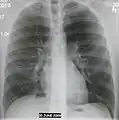

AP CXR showing left lower lobe pneumonia associated with a small left sided pleural effusion